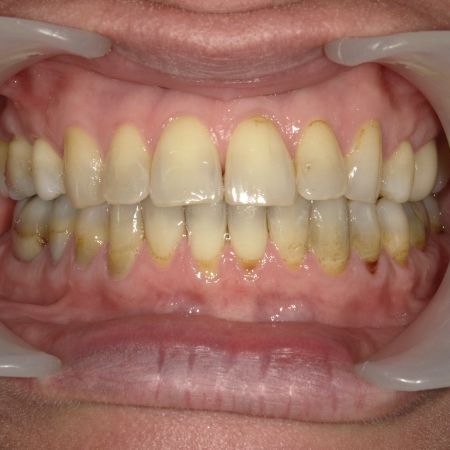

Während der Behandlung

Links Zustand beim Einsetzen der festen Zahnspange, rechts Situation unmittelbar nach der Operation (nach 2 Jahren, 4 Monaten). Der Unterkiefer wurde chirurgisch vorgesetzt und dadurch die Zahnreihen besser in Kontakt gebracht. Die Operation wurde an der Uniklinik Homburg durchgeführt. Eine Feineinstellung der Verzahnung ist aber im Laufe der kieferorthopädischen Nachbehandlung noch erforderlich.